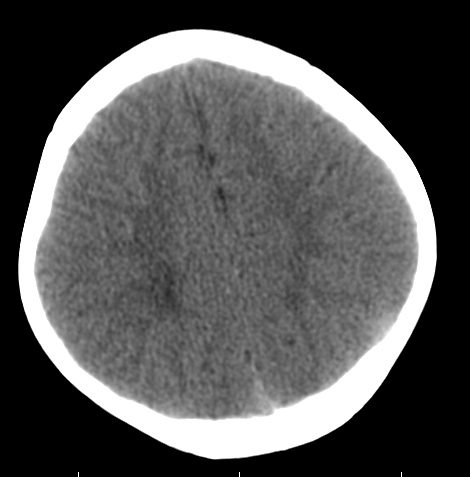

女,3岁,头部外伤一小时。半卵圆中心低密度是什么意思,病灶?侧脑室?请指教。

正常表现

幼儿正常脑白质表现,长期观察,必要时mr

从层面看不是侧脑室,考虑低密度变,建议mri。

不是侧脑室,考虑正常脑白质。为慎重,建议mr!